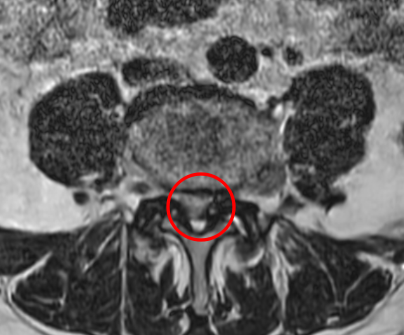

腰痛MRIを確認したところ、L3/4と、L4/5の2か所に腰椎すべり症が原因とみられる脊柱管狭窄症を認めました。L4/5は特に狭窄が酷くなっていました。

治療では、痛みの原因だと考えられるL4/5の狭窄を取り除く手術「PEL」を局所麻酔下のもとで実施し、神経の圧迫を取り除きました。最後には、神経細胞の修復作用効果と、患部の修復促進効果を期待して、再生医療「PRP療法」を施しました。

手術の翌日には、座っていると少し痛みが出るものの、これまであった左足の痛みはなくなったそうです。さらに術後1か月目には腰痛は10から2に、足の痛みは10から0になりました。術後の腰椎MRIでもL4/5が減圧していることを確認しました。さらに術後2か月目は、腰痛の痛み指数も0になりました。